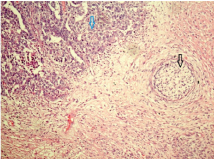

Among the non-seminomatous tumours, mixed germ cell tumour was the most frequent subgroup accounting for 85.8% followed by yolk sac tumour and teratoma. The predominance of mixed germ cell tumours among non-seminomatous tumours have also been reported in Turkey [26]. However, in another study from Ilorin, Nigeria yolk sac tumour was the most common subtype [27]. The most common combination in our study was teratocarcinoma (teratocarcinoma with embryonal carcinoma) accounting for 6/12 cases (50%) followed by 4/12 cases (33.3%) of teratocarcinoma with yolk sac tumour and 2/12 cases (16.7%) of seminoma with yolk sac tumour. Our findings were in accordance with previous study in which teratocarcinoma was commonest subtype [10]. Gross examination of most of the teratocarciomas revealed variegated appearance ranging from 5.5 to 11 cm in diameter. Microscopic examination revealed mostly teratomatous and embryonal carcinomatous elements [Table/Fig-7,8].

Scanner view of mixed germ cell tumour showing teratomatous (black arrow) and embryonal carcinomatous (blue arrow) component. (H & E- 40x).

Low power view of mixed germ cell tumour showing teratomatous (black arrow) and embryonal carcinomatous (blue arrow) component. (H & E- 100x).